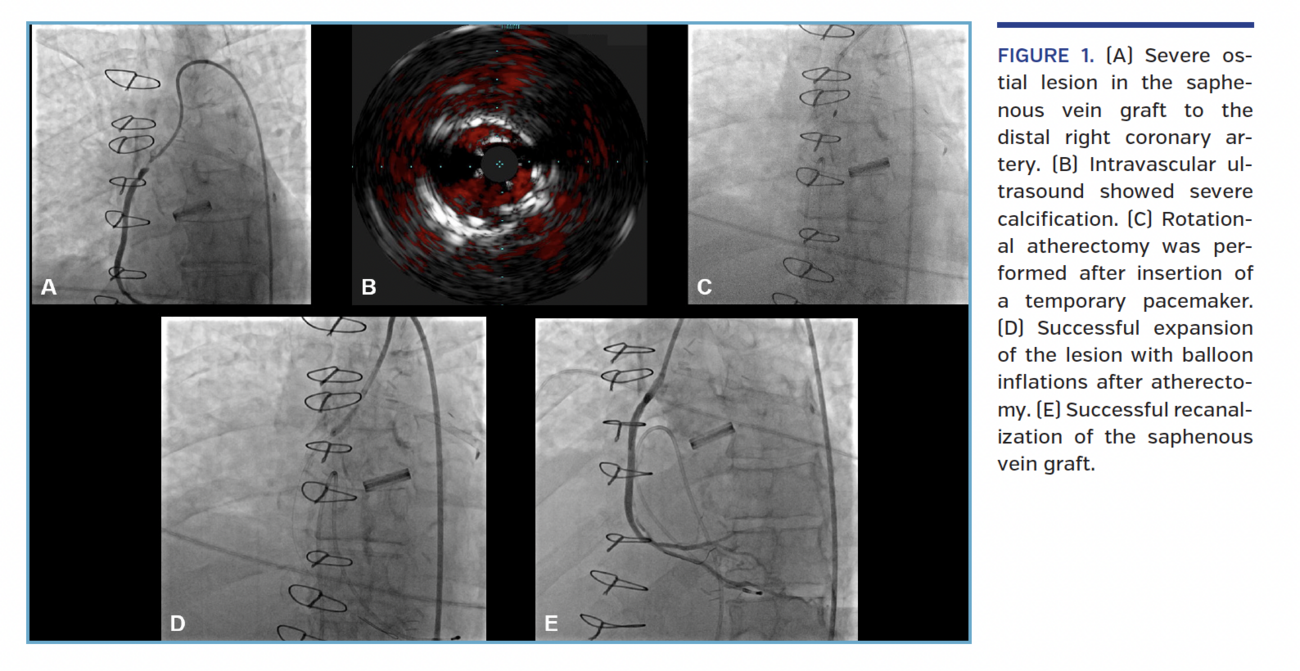

Emergent cardiac catheterization showed chronic total occlusion of the left main and proximal right coronary artery (RCA) and an atretic left internal mammary graft to the mid left anterior descending artery. The saphenous vein graft (SVG) to the first obtuse marginal was patent. The SVG to the distal RCA had severe ostial stenosis (Figure 1A; Video 1).

Engaging the SVG to RCA was challenging due to stent underexpansion, but eventually successful using a multipurpose diagnostic catheter to insert a Grand Slam guidewire (Asahi Intecc), followed by exchange for a 7 Fr multipurpose guide catheter. Inflation of 2.5 and 3.0 mm balloons and a 3.0 Angiosculpt (Philips) failed to expand the lesion. Intravascular ultrasound showed severe calcification (Figure 1B; Video 2). A temporary transvenous pacemaker was inserted and rotational atherectomy was performed with a 1.5 mm burr (Figure 1C; Video 3). The lesion was crossed after 13 runs. Multiple balloon dilations were performed (Figure 1D; Video 4), causing transient hypotension, and a 3 x 30 mm drug-eluting stent was deployed at 26 atm, achieving a good result with TIMI 3 flow (Figure 1E; Video 5). Echocardiography after 1 month demonstrated ejection fraction improvement.